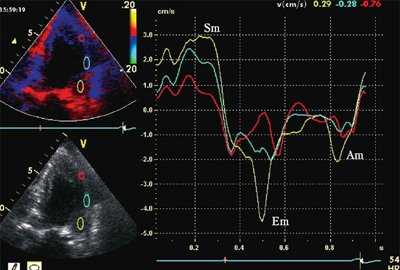

На рис. 3-5 приведены различные варианты ПСУ у больных с постинфарктным кардиосклерозом.

![Тканевая допплерография в норме. У больного с постинфарктным кардиосклерозом регистрируется высокоамплитудный пик постсистолической скорости (Sps)]()

![Тканевая допплерография при постинфарктном кардиосклерозе. У больного с постинфарктным кардиосклерозом регистрируется высокоамплитудный пик постсистолической скорости (Sps)]()

б) При постинфарктном кардиосклерозе. У больного с регистрируется высокоамплитудный пик постсистолической скорости (Sps).

Вертикальная линия (AV) на рис. 3-5 соответствует времени закрытия аортального клапана. На представленных графиках также отмечается наличие базально-верхушечного градиента (снижение пиковых миокардиальных скоростей, продольного систолического смещения и деформации от основания к верхушке левого желудочка).

Достоверных различий между гипо- и акинетичными сегментами по характеристикам ПСУ не было выявлено, хотя в подгруппе акинетичных сегментов ПСУ регистрировалось несколько чаще. В нормокинетичных сегментах у больных с постинфарктным кардиосклерозом пики Sps и STps определялись значительно чаще, чем в контрольной группе (53 и 30% в сравнении с 18 и 2% случаев соответственно; p<0,05). ПСУ также было выявлено в 68% точек митрального кольца, расположенных у основания стенок левого желудочка с нарушенной сократимостью.